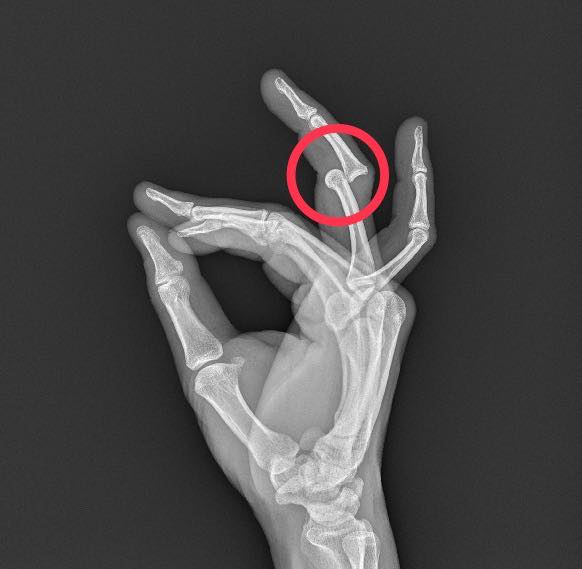

前幾天一位患者因為清洗水池不慎跌落,手指受到強烈的撞擊。來到我們診所的時候,受傷的部位已經明顯腫脹變形,照完 X 光片才發現,關節已經有脫臼的情況

這類手指關節脫臼,其實常常會伴隨骨頭的撕脫性骨折,因為脫臼的瞬間,韌帶會猛力拉扯它附著的骨頭,把一小塊骨頭扯下來。好在這位患者的 X 光片確認只是單純的脫臼,沒有合併骨折